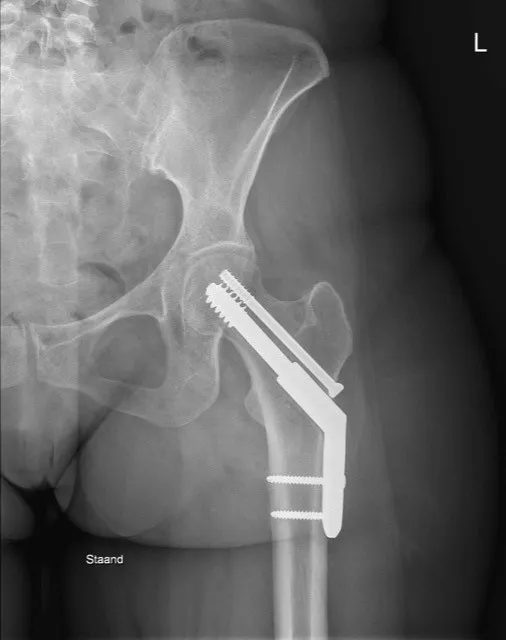

1. Intramedullaire heupnagel (gammanagel)

Bij een pertrochantere of subtrochantere femurfractuur is een intramedullaire nagel vaak de voorkeursbehandeling. Hierbij wordt een stevige metalen pen ingebracht via het bovenste deel van het dijbeen (femur), in het beenmergkanaal. Deze ‘gammanagel’ wordt verankerd met een dwarsschroef in de hals en kop van het dijbeen en 1 of 2 schroeven lager in het bovenbeen. Dit biedt een stevige fixatie voor patiënten die snel weer moeten mobiliseren en geeft minder risico op loslating bij osteoporotisch bot.